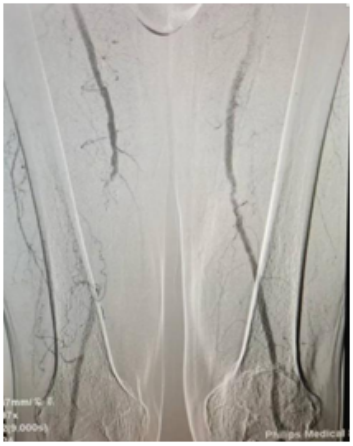

患者是一名74岁的男性,在1个半月前无明显诱因的出现右下肢间歇性跛行,逐渐加重,行走距离逐渐缩短,休息时仍有疼痛,入院后DSA造影结果提示右股浅动脉中下段闭塞改变,考虑患者症状为下肢动脉缺血所致,需要开通闭塞血管恢复血流。

△造影提示右股浅动脉中下段闭塞